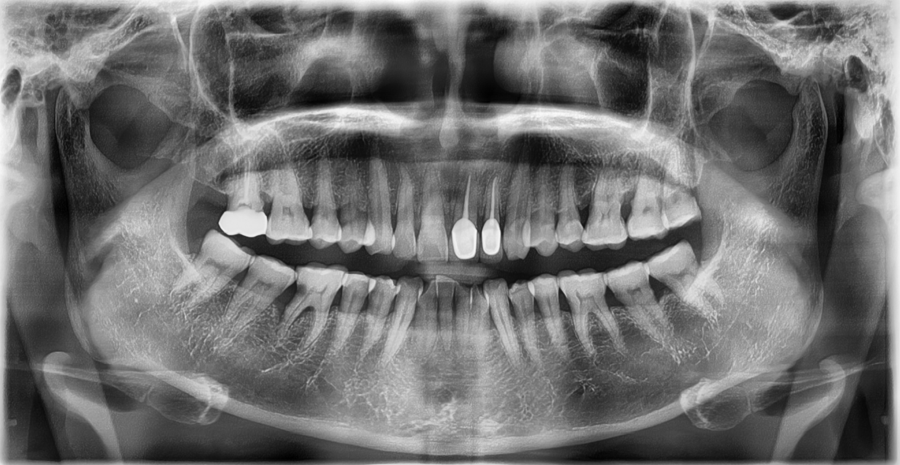

The patient had already undergone

prosthetic treatment for the front teeth and implant treatment for the molars.

Previous image

Next image